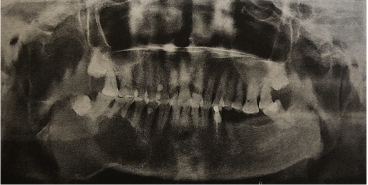

以下圖為例:

上圖是右下頜骨的成釉細(xì)胞瘤,全景片顯示右下頜骨體部及升支多囊性、透射性改變,邊界清楚;下頜角區(qū)頜骨膨隆,46及47牙根截?cái)酄钗铡?